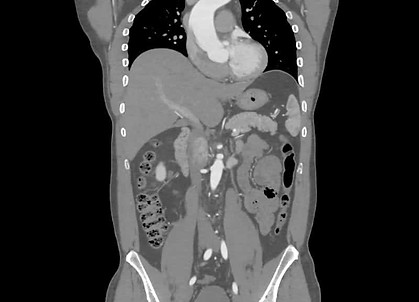

Colonoscopies, fecal occult blood tests, sigmoidoscopies, and barium enemas are known for their use as screening tools for the early detection of colorectal cancer,1 yet many people still find these procedures over age 50 get screened for colon polyps. A 1995 survey even found that people who had never had a colonoscopy would rather give up 3 months of life than undergo the test.2

In the face of such obvious patient aversion, virtual colonoscopya more comfortable yet still effective screening examination performed using a multidetector CT (MDCT) scanis emerging as an alternative that may open the door to a much higher patient participation rate.